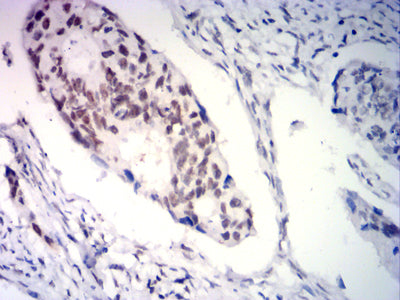

分类: 科研抗体货号: 31933别名: PR; NR3C3应用: WB,IHC,FCM反应种属: Human